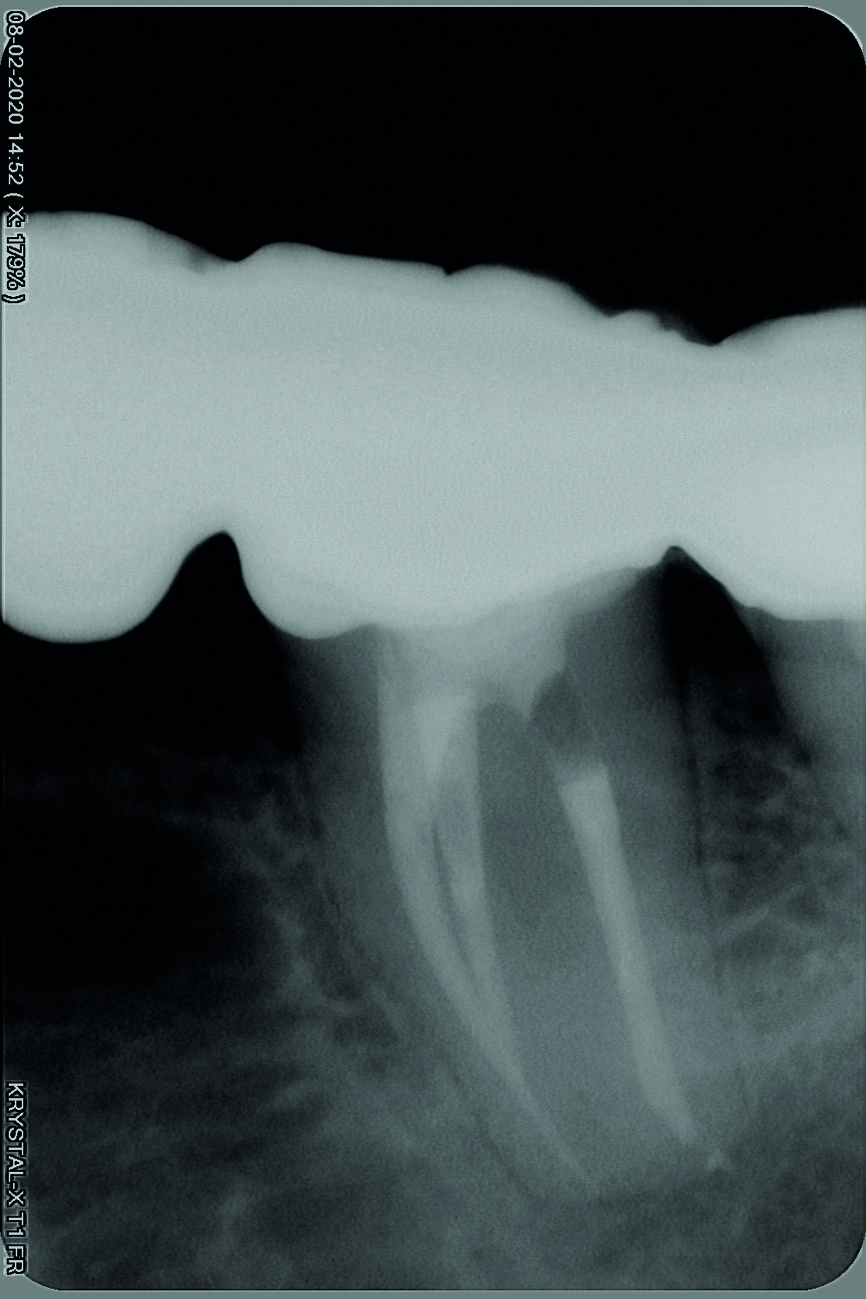

Une anesthésie locale est réalisée, la dent est isolée avec une digue et la cavité d’accès est préparée. L’obturation en gutta-percha située en coronaire du fragment est éliminée au moyen d’une pièce à main sonique (SONICflex 2003 L, KaVo) et de limes Micro Type D (MANI), sous examen microscopique direct (Fig. 2). Ensuite, une plate-forme de travail périphérique est préparée au niveau de l’extrémité coronaire du fragment. Pour ce faire, une fraise Gates–Glidden modifiée de taille 3 (MANI ; Fig. 3) est utilisée à basse vitesse de rotation de 300 trs/min et dirigée apicalement jusqu’à entrer en contact avec le fragment instrumental fracturé. La procédure est réalisée dans chaque canal (Figs. 4 et 5). La plate-forme doit être légèrement plus large que le diamètre coronaire du fragment (Fig. 6). Un espace est créé autour du fragment au moyen d’une pièce à main sonique (SONICflex Quick 2008 L, KaVo) munie d’un insert Endo Clean de taille 25 (portion coronaire exposée sur 2 mm). Au cours de cette étape, le même insert est utilisé pour émousser la partie active (lames) de l’instrument fracturé, afin d’éviter d’endommager la boucle du fil métallique (Figs. 7a et b) qui servira de lasso.

Fig. 5 : Radiographie après retrait de la partie coronaire de gutta-percha et création d’une plate-forme de travail

Fig. 13 : Radiographie après retrait du fragment.